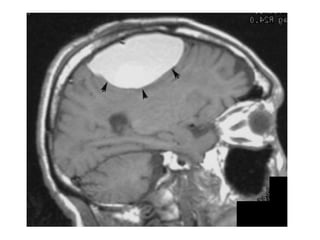

N.B. :

Fogging Phenomenon

-Is seen on non contrast CT of the brain and

represents a transient phase of the evolution of

cerebral infarct where the region of cortical

infarction regains a near normal appearance

-During the first week following a cortical

infarct hypoattenuation and swelling become

more marked resulting in significant mass effect

and clear demarkation of the infarct with vivid

gyral enhancement usually seen at this time

-As time goes on the swelling starts to subside and

the cortex begins to increase in attenuation , this

is believed to occur as the result of migration into

the infarcted tissue of lipid-laden macrophages as

well as proliferation of capillaries and decrease in

the amount of edema

-After 2 to 3 weeks following an infarct the cortex

regains near-normal density and imaging at this

time can lead to confusion or missed diagnosis

-Fogging has been demonstrated in around 50% of

cases

-If in doubt the administration of IV contrast

will demarcate the region of infarction

-A similar phenomenon is also seen on T2 weighted

sequences on MRI of the brain and is believed to

be due to similar cellular processes, as the timing

is similar , it has been found to occur in

approximately 50% of patients between 6 and 36

days (median 10 days) after onset of infarction

2 Days post onset of

symptoms

9 days post onset of symptoms